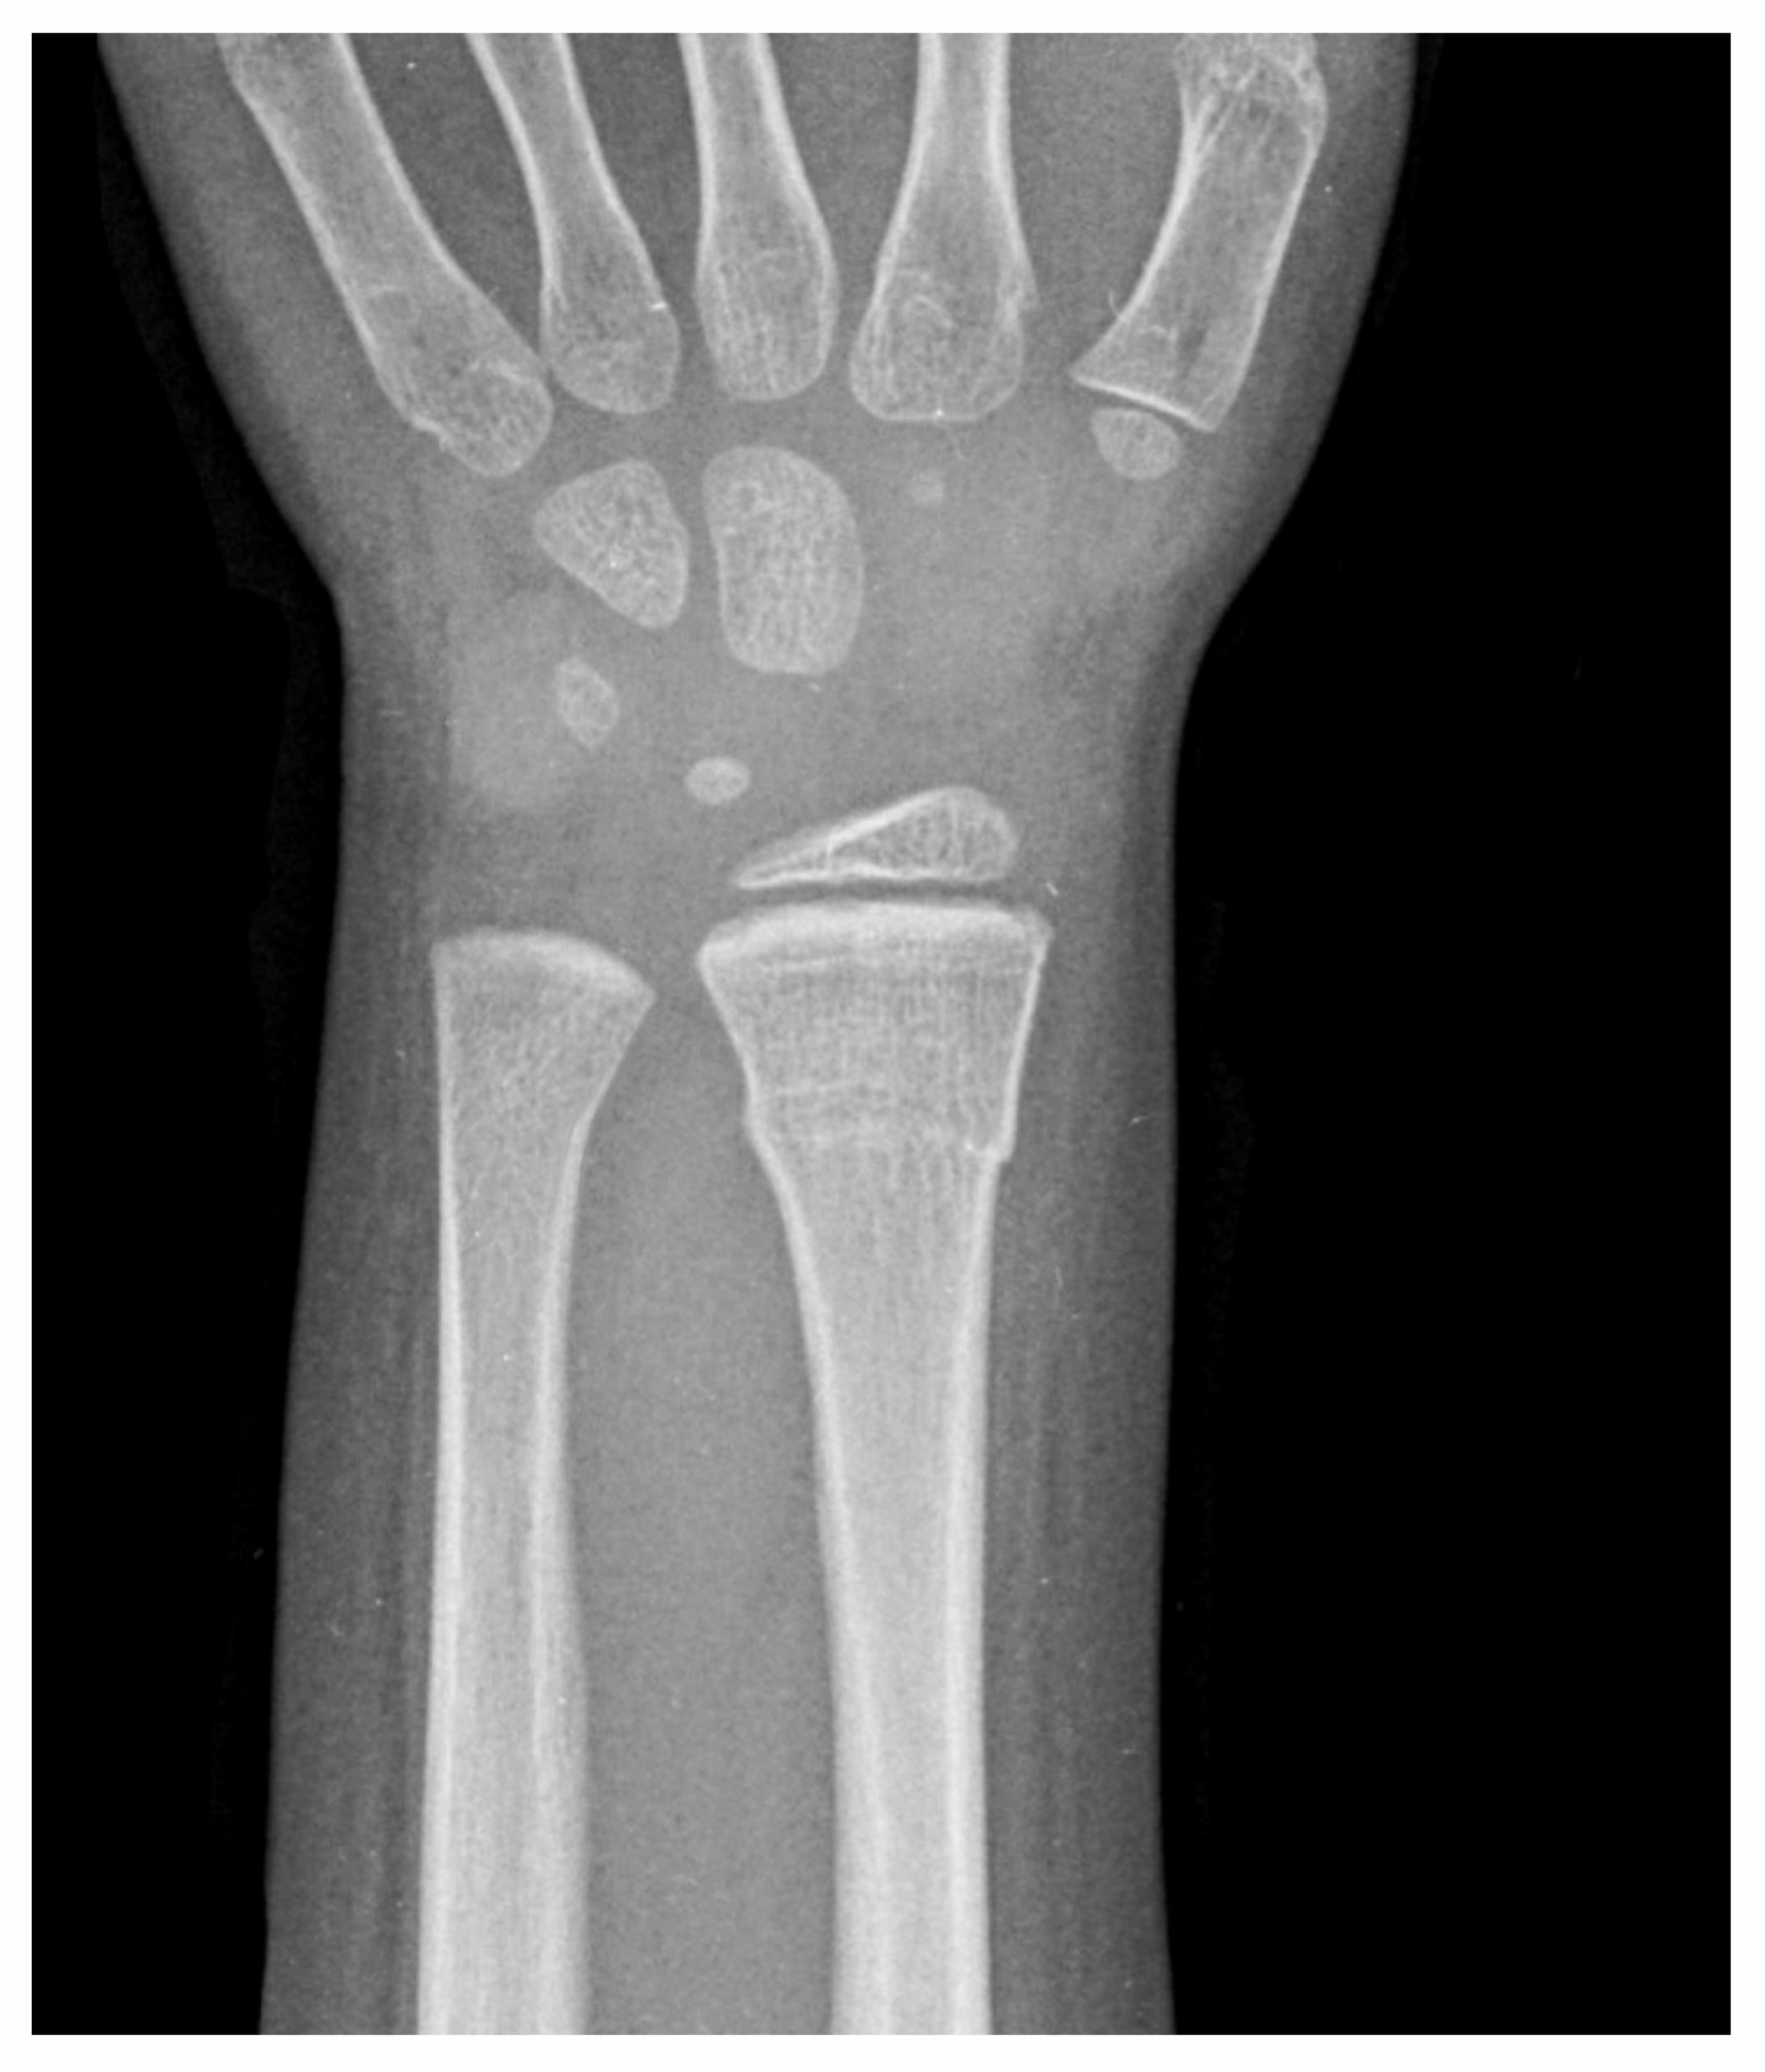

A 5-year-old girl presents to the ED with her parents for arm pain after a fall. Her age and general shyness makes a full history and review of systems difficult. Her parents report she was found next to the couch crying. They assume she fell off onto her arm. She now does not want to move her arm. She has no other evidence of trauma on her physical exam. X-rays of her forearm are shown above. What is this fracture called?

Torus (Buckle) Fracture